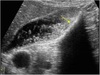

●Rare form of acute cholecystitis ●Gas-forming bacteria invade GB wall, lumen, pericholecystic spaces, and occasionally bile ducts ●More common in men ●As many as 40% of cases associated with diabetes ●Gallstones not seen in many cases—more common in acute cases ●Patients present with sudden progressive RUQ pain, fever, nausea, and vomiting ●Patients likely to develop a gangrenous GB or abscess formation ●GB perforation can also occur ●Fatal in about 15% of cases ●Sonographic appearance: ➢Gas bubbles are prominent non–gravity-dependent changing position with patient position ➢Air appears as echogenic foci within GB wall or lumen—causes GB wall to appear echogenic ➢Ring down or comet tail artifacts are seen ➢Artifacts may make it difficult to visualize GB

Emphysematous Cholecystitis